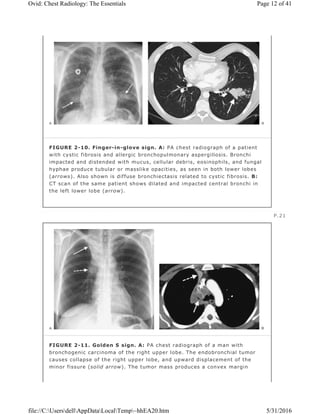

FIGURE 2-10. Finger-in-glove sign. A: PA chest radiograph of a patient

with cystic fibrosis and allergic bronchopulmonary aspergillosis. Bronchi

impacted and distended with mucus, cellular debris, eosinophils, and fungal

hyphae produce tubular or masslike opacities, as seen in both lower lobes

(arrows). Also shown is diffuse bronchiectasis related to cystic fibrosis. B:

CT scan of the same patient shows dilated and impacted central bronchi in

the left lower lobe (arrow).

Finger-in-Glove Sign

Aspergillus hypersensitivity, the bronchi become impacted with mucus, cellular

debris, eosinophils, and fungal hyphae. The impacted bronchi appear

radiographically as opacities with distinctive shapes (Fig. 2-10), variously

described as “gloved finger,†“Y,†“V,†“inverted V,â€

“toothpaste,†and so forth (8).